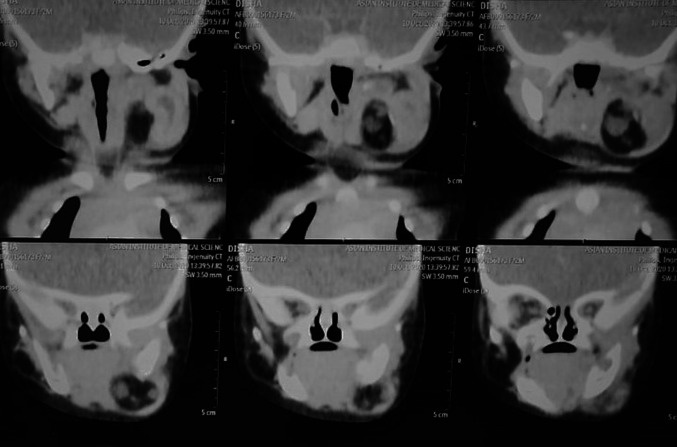

Fig. 2.

CECT neck showing multiple calcified areas mixed with cystic spaces

A 2 month old female child presented to the ENT OPD with complaints of a progressively increasing left sided neck swelling since birth. The mother also complained of the child having difficulty in feeding for the last 10 days. There was no history of breathing difficulty, noisy breathing or cyanosis. Rest of the history was unremarkable. On examination, there was a globular, cystic, mobile, non-tender mass measuring 5 × 5 cm with well-defined margins observed in the left submandibular region. The overlying skin was normal. (Fig. 1) Intra oral examination showed presence of left buccal mucosa bulge. Contrast enhanced Computed Tomography showed a well-defined lesion showing fat density, a few calcified foci along with heterogeneously enhancing components in the left submandibular region measuring 5 × 4.1 × 3.1, suggestive of teratoma. (Fig. 2) Pre-operative FNAC was suggestive of a lipomatous lesion. The patient was planned for excision of the mass under general anaesthesia. Intraoperative findings included a well capsulated mass extending up to the floor of the mouth. All the vital neurovascular structures were preserved and the mass was removed in toto along with the ipsilateral submandibular gland. Grossly it was 4 × 4.5 × 3 cm size encapsulated solid mass with a pale yellow bosselated surface possibly extending into the submandibular gland. (Fig. 3) Microscopic examination of the specimen showed features of mature cystic teratoma. (Fig. 4).